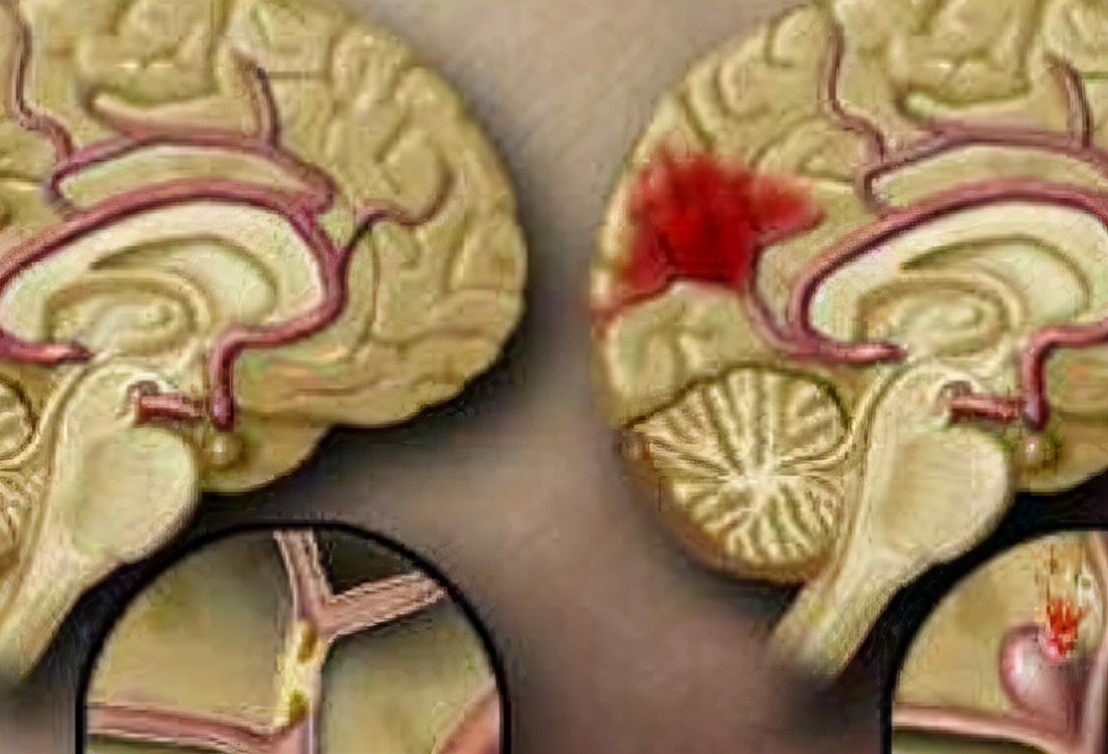

一、脑出血是什么?

脑出血是指原发性非外伤性的脑实质出血。绝大部分的患者发病部位发生于大脑半球,极小部分的患者发生于脑干和小脑。 生活中脑出血的发病原因复杂,多半主要跟脑血管的病变有关。

另外,脑出血属于神经性疾病,由于长期在高血压的作用下会造成血管破坏,从而引起出血。 脑出血发生时,病人会迅速地出现肢体不协调,言语不清,意识昏迷的临床表现 。

作为早期诊断脑出血的唯一治疗手段,它的准确性非常高。检查颅脑时, 颅内出现高密度影像时,就可以判断此人患上脑出血; 极少数个别情况的患者由于脑出血的面积很小,不易被察觉。